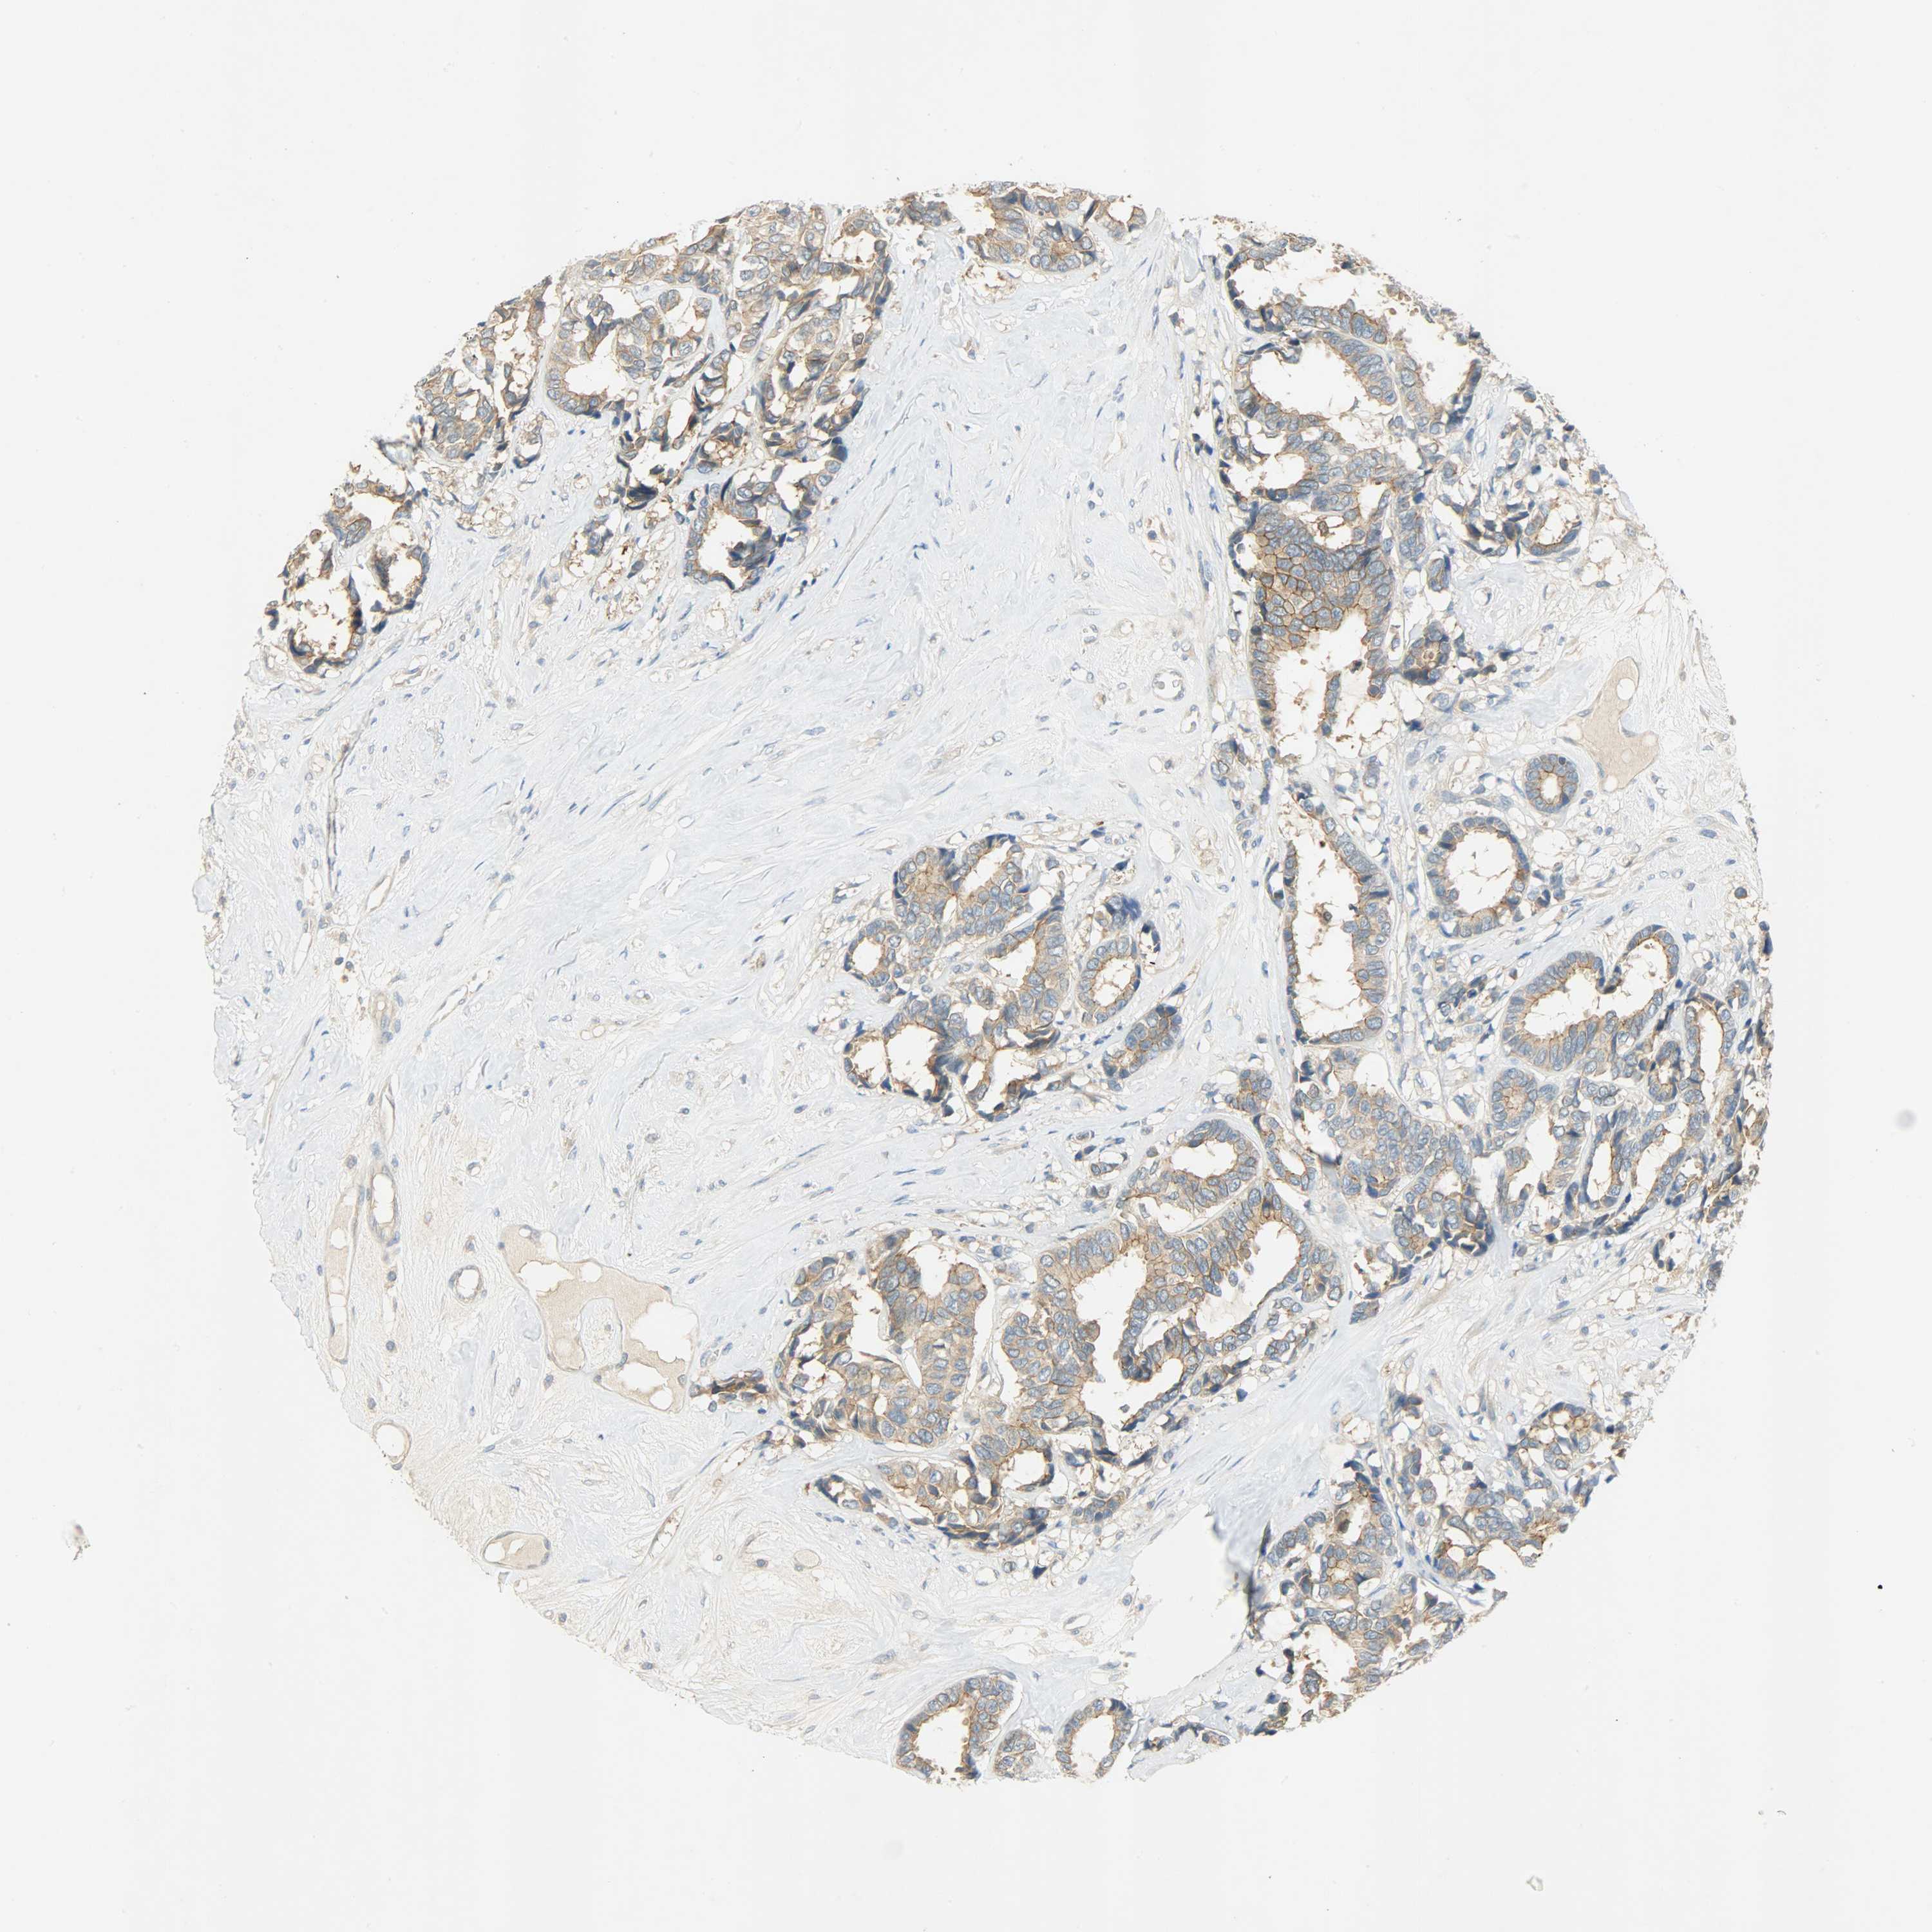

CANCER BREAST CANCER Show tissue menu

BRCA TCGA BRCA VALIDATION PROTEIN EXPRESSION